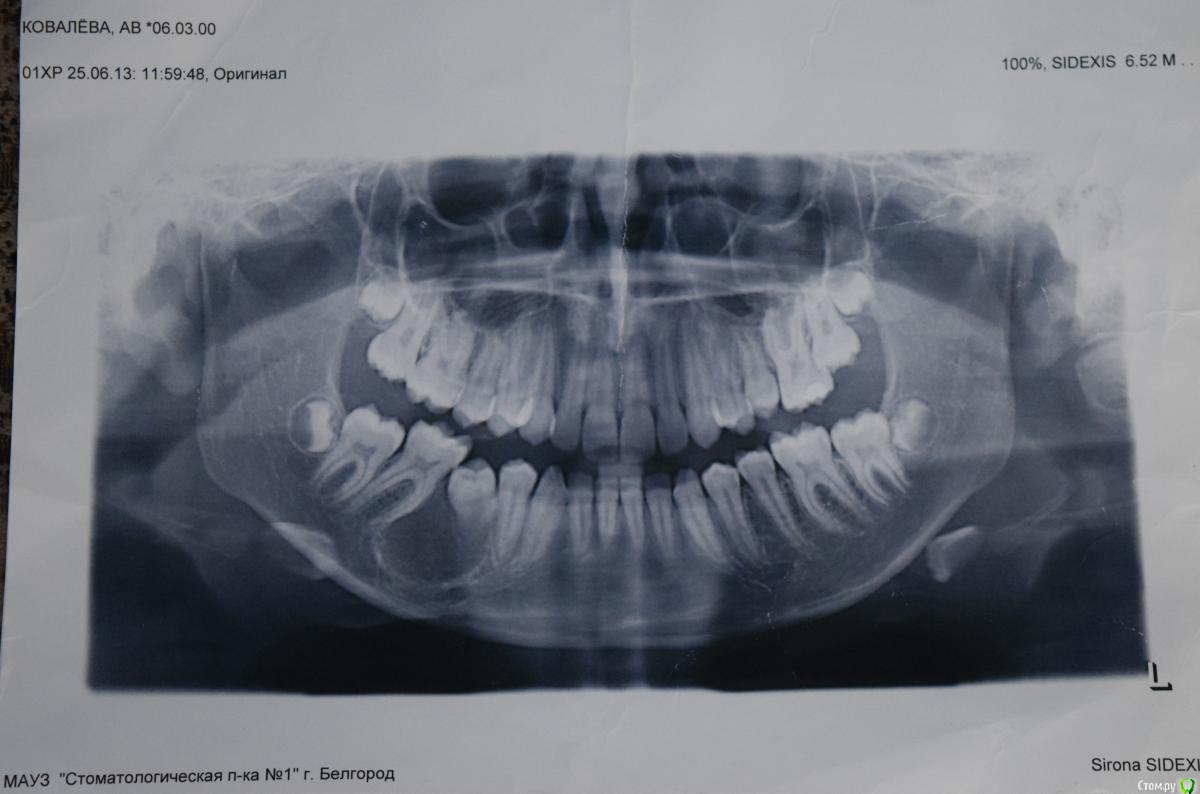

Kovalov Igor Опубликовано 14 июля, 2015 Поделиться Опубликовано 14 июля, 2015 (изменено) Уважаемые коллеги приветствую Вас! Встал вопрос стоит ли трогать фолликулярную кисту или наблюдать?Пациентка моя сестра, фолликулярная киста была случайной находкой, обнаружил ортодонт, отправил в областную больницу г. БелгородаВ детской ЧЛХ отказались, отправили в Харьков, это был 2013 год ещё. Во взрослой ЧЛХ не взялись, по возрасту. В детской члх сделали КТ, снимки и панораму прилагаю.Ps: картина за 2 года стала получше, но КТ сделают позже, есть внеротовой Rg снимок. Дело в том что я живу от сестры более 3000 км., сам бы это дело вскрыл амбулаторно, цистэктомия, графт+мембрана если гноя не будет... либо под йодоформом. Но вопрос стоит ли? и как по протоколу, каков Ваш план лечения? Депульпировать ли зубы 45-46? Изменено 14 июля, 2015 пользователем Kovalov Igor Ссылка на комментарий

Kovalov Igor Опубликовано 14 июля, 2015 Автор Поделиться Опубликовано 14 июля, 2015 вот Rg свежий. Вроде граница фолликулярной кисты уменьшилась.Как сделают КТ поделюсь тут... Буду признателен за ответы! Ссылка на комментарий